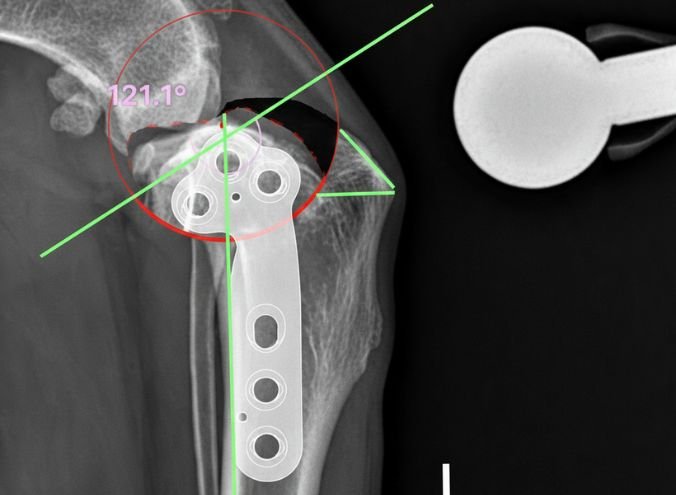

Cirugía TPLO

Pioneros en la zona en la realización de la técnica Tibial Plateau Leveling Osteotomy para el tratamiento de la ruptura de ligamento craneal cruzado, orientada a la recuperación de la movilidad total del paciente.

Traumatología y Ortopedia

Consulta especializada y resolución quirúrgica de patologías del sistema musculoesquelético, incluyendo displasia de cadera, fracturas complejas y afecciones en huesos largos.